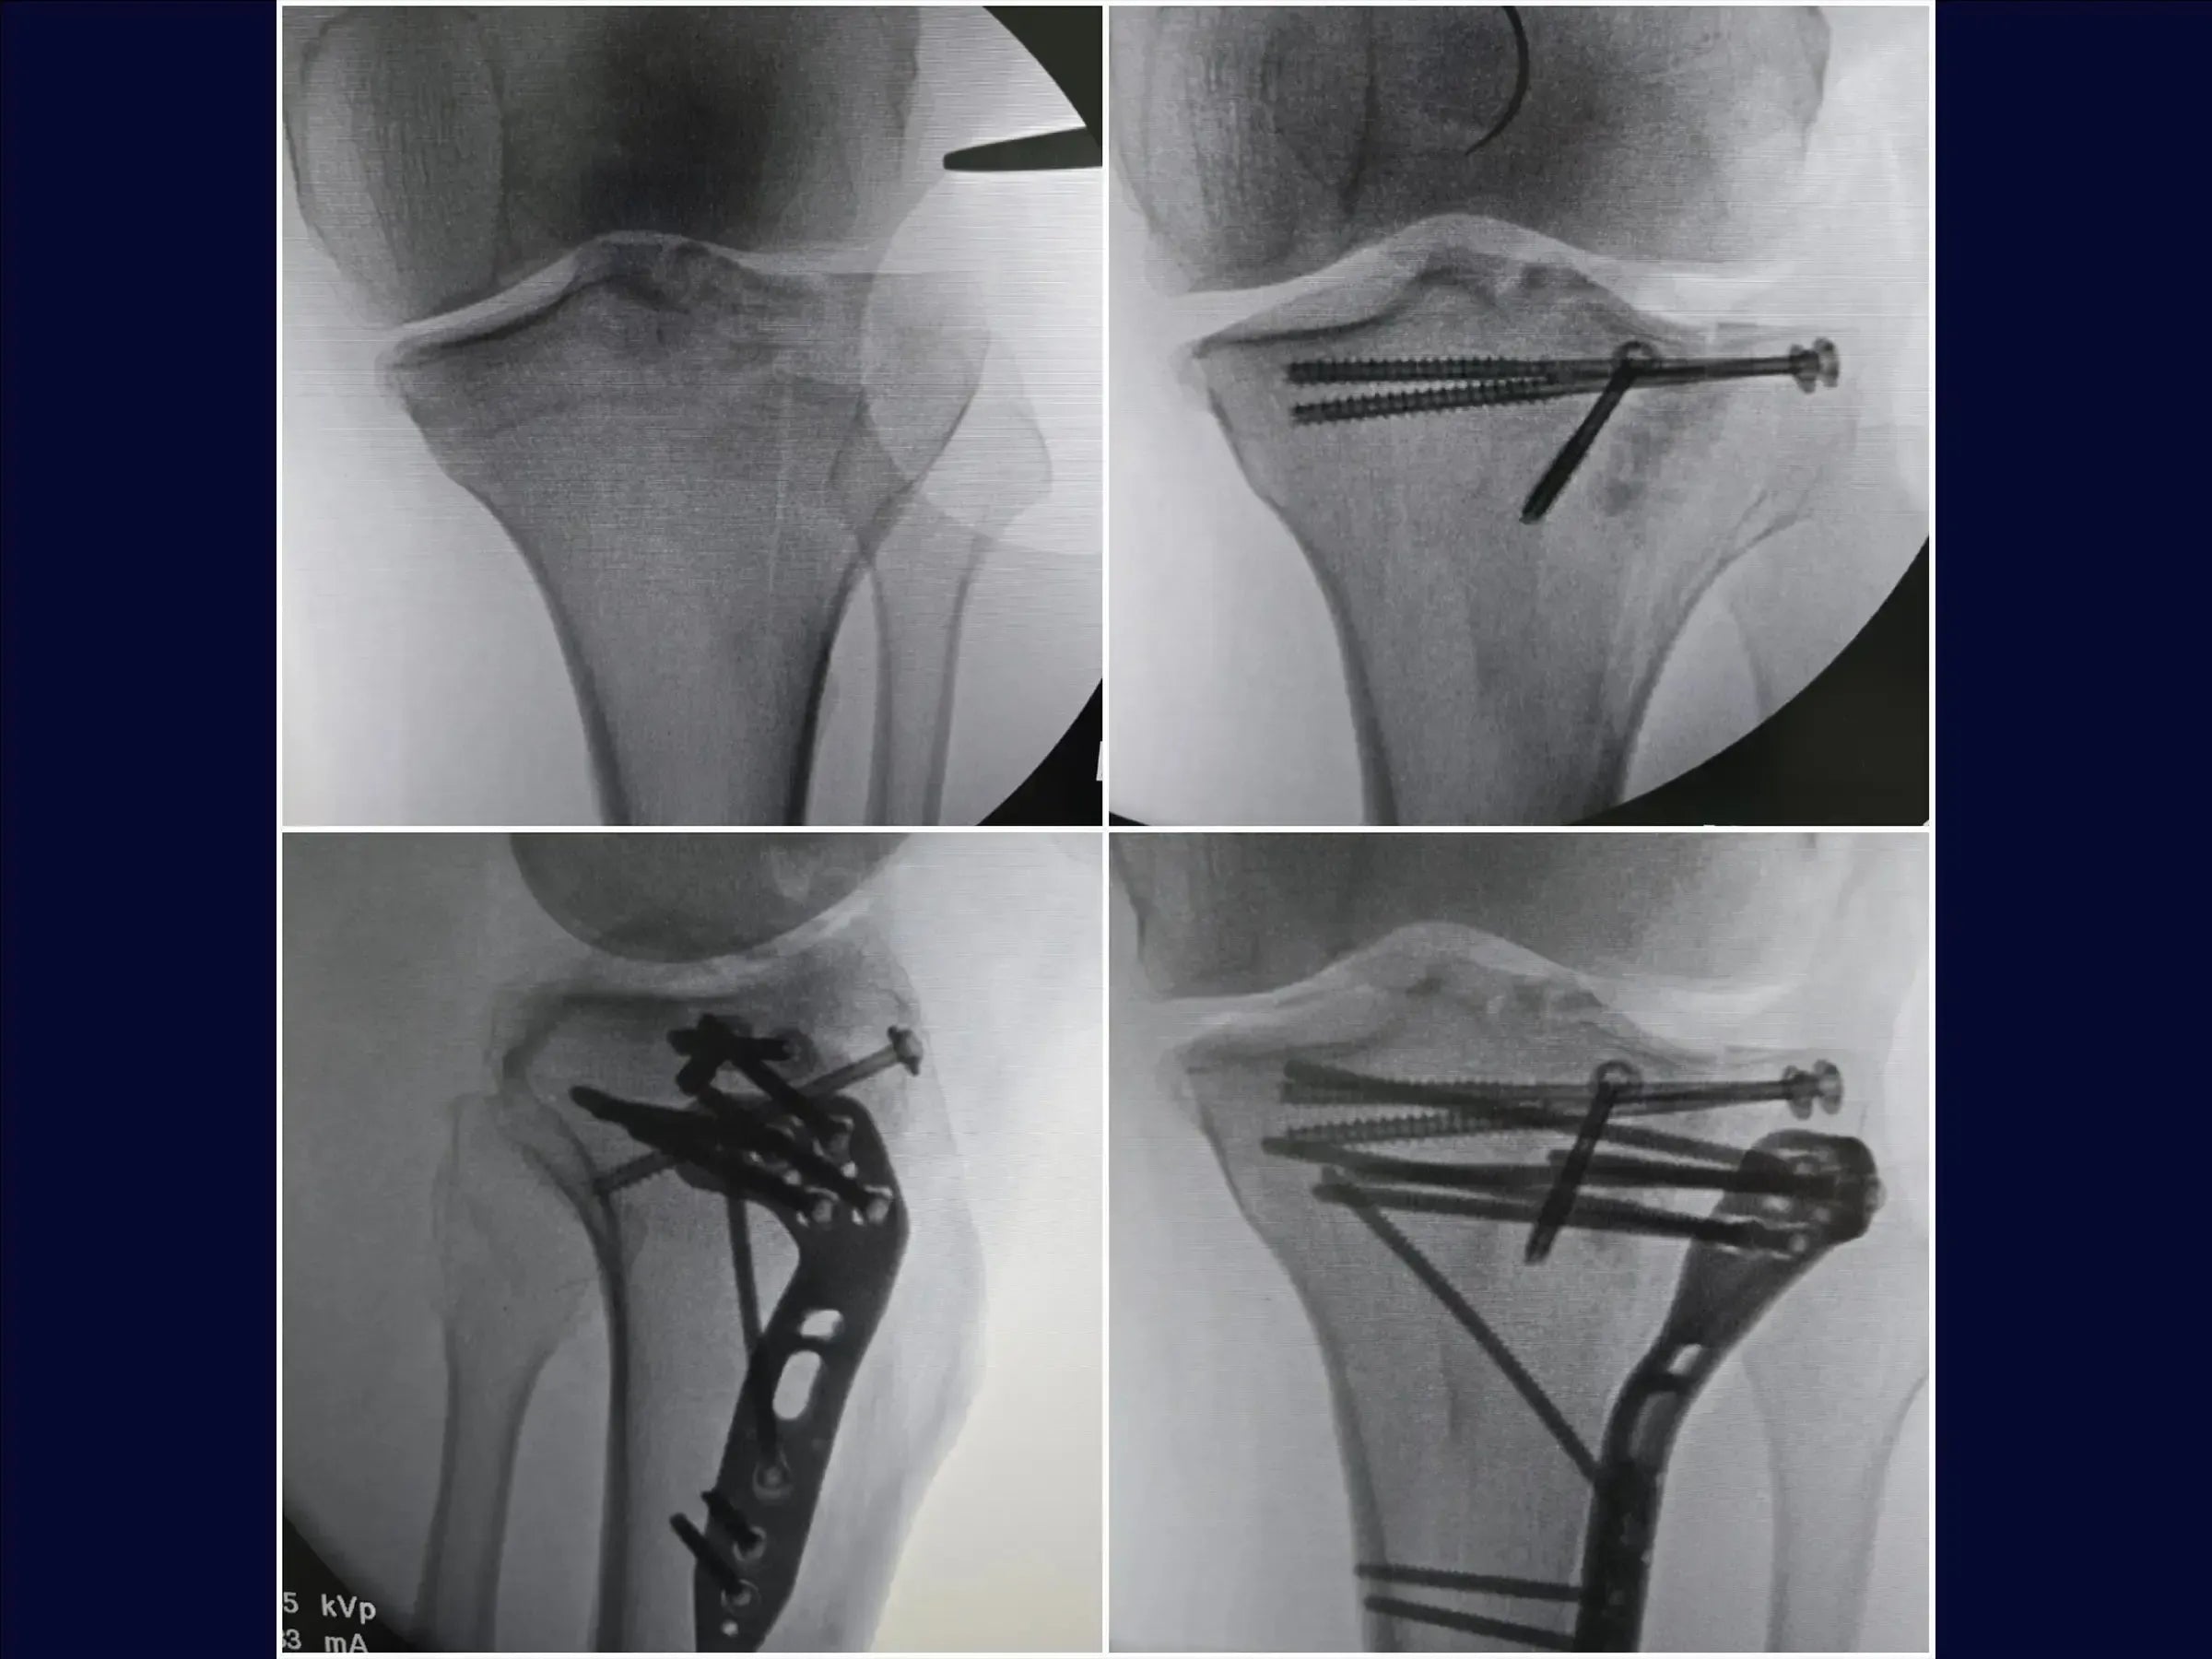

- Osteossíntese de fraturas do platô tibial com afundamento central e cisalhamento incompleto.

- Acesso anterolateral em "taco de hóquei" para exposição ampla.

- Utilização de enxerto ósseo estrutural e fixação com parafusos canulados subcondrais e placa.

- Acesso Cirúrgico Otimizado: Metodologia para marcação e incisão em "taco de hóquei", facilitando a exploração articular e o fechamento estético da pele.

- Osteotomia Elástica para Redução Anatômica: Abordagem de osteotomia incompleta que mantém a cortical anterolateral íntegra, permitindo o levantamento do fragmento afundado com retorno natural à posição.

- Estratégias de Enxertia Óssea: Protocolos para preenchimento da depressão com enxerto em grânulos, incluindo hipercorreção para acomodação e resistência, e uso de enxerto estrutural para suporte.

- Fixação Estável e Rede Subcondral: Posicionamento de fios guia para parafusos canulados subcondrais, criando uma "rede" para estabilidade primária, e utilização estratégica da placa para compressão e manutenção do levantamento.

- PDF Detalhado: Resumo prático do procedimento, abordando: condição da fratura (platô tibial com afundamento central e cisalhamento incompleto); acesso cirúrgico anterolateral em "taco de hóquei"; preparação e dissecção detalhada; manuseio do menisco e osteotomia incompleta (elástica); levantamento da depressão e enxertia; fixação com parafusos canulados e placa; e fechamento por planos para restauração anatômica e tecidual, culminando em redução anatômica e boa estabilização.